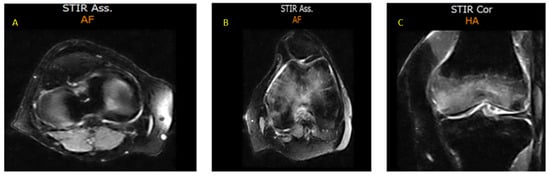

- CASE 1: A CML patient under dasatinib and imatinib treatment

- CASE 2: 60-year-old patient with imatinib therapy

- CASE 3: 66-year-old patient with imatinib therapy